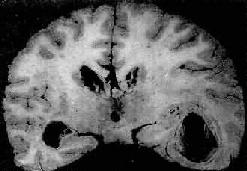

脑脓肿的发展规律和形态与全身其它器官的脓肿相似。急性脓肿发展迅速,境界不清,无包膜形成,可向四周扩大,甚至破入蛛网膜下腔或脑室,引起脑室积脓,可迅速致死。慢性脓肿边缘毛细血管和纤维母细胞(源于血管壁)增生明显,并伴有淋巴细胞和巨噬细胞浸润,形成炎性肉芽组织和纤维包膜,境界清楚。脓肿周围脑组织水肿明显,并伴有星形胶质细胞增生(图16-12)。

慢性脑脓肿

图16-12 慢性脑脓肿

右侧颞叶的脑脓肿与侧脑室相通